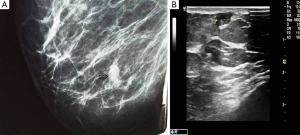

Mammography showed a relatively well-defined mass with sparse calcifications (Figure 1A), whereas ultrasonography revealed a circumscribed microlobulated hypoechoic mass measuring 1cm without posterior acoustic enhancement (Figure 1B). On color Doppler examination the mass exhibited marked hypervascularity (Figure 2A). A breast magnetic resonance imaging (MRI) was obtained and demonstrated a nodule measuring 1cm with partially irregular margins located 9 cm from the nipple in the lower inner quadrant of the right breast (Figure 2B). After contrast administration a rapid increase of the signal intensity was noted followed by a wash out curve in the delayed phase and thus the lesion was classified as BIRADS category 5. Cytology examination was not performed because a repeated aspiration of the nodule yielded only blood.

At mammography, breast hemangioma may appear as a well-defined, circumscribed or microlobulated mass isodense to the surrounding breast parenchyma (4,11). In some cases, the tumor may be difficult to be seen on craniocaudal or mediolateral oblique views and thus a tangential view may be necessary for evaluation (7). Mammography may have additional limitations, especially in young patients, due to the dense parenchymal pattern (2). The mass may rarely contain microcalcifications (1,3,5,6) of fine, punctuate or phlebolith pattern (3). The presence of microcalcifications on both mammogram and ultrasonography is a factor that may suggest a malignant process (9).

On ultrasonography, breast hemangioma may have a variable appearance. It most commonly appears as a superficially located oval mass with parallel orientation and circumscribed margins. Internal echostructure is variable and the tumor can be hypoechoic, isoechoic or hyperechoic (1,3-5,11). Compressibility of the tumor may be detected only in the absence of thrombosis (7). In some cases an isoechoic tumor cannot be clearly displayed from the surrounding adipose tissue (5). Although the vascularity of the tumor has not been reported to have diagnostic value (2), the presence of hypervascularity may indicate a suspicious of malignancy tumor (7).